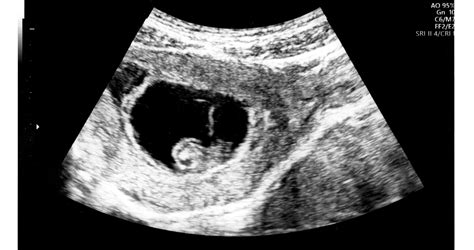

A méhlepény egészsége a magzat fejlődésének kulcsa. Mikor vizsgáljuk a méhlepényt? A méhlepény ellenőrzése nem egyetlen alkalomra korlátozódik; a terhességi ultrahang protokoll minden szakaszában más és más szempont kerül előtérbe. Bár az első trimeszterben (kb. a 12. hétig) a placenta még csak formálódik, az ultrahang már ekkor adhat jelzéseket. A méhlepény korai fejlődésének vizsgálata indirekt módon történik, főként a beágyazódás helyének és a chorion bolyhok állapotának felmérésén keresztül. Ekkor derülhet ki például, ha a terhesség nem a méhben (ectopiás terhesség) vagy a méhnyak közelében (pl. A 11-13. hét körüli első genetikai ultrahang során a méhlepény vastagságát és homogenitását is vizsgálják. Bármilyen szokatlan struktúra vagy abnormális folyadékgyülem felvetheti a korai lepényi zavar lehetőségét, ami további genetikai szűréseket indokolhat.

A második trimeszter közepe, különösen a 18-22. hét közötti anatómiai ultrahang, a méhlepény vizsgálatának legkritikusabb szakasza. Ekkor történik meg a placenta végleges helyzetének és struktúrájának részletes felmérése. Lokalizáció: Hol tapad a méhlepény (elülső, hátsó, fundus, oldalsó). A legfontosabb szempont a méhszájhoz viszonyított távolság. Vastagság és homogenitás: A placenta vastagsága a terhességi korhoz képest megfelelő-e. Cord insertio: A köldökzsinór beágyazódási helye a placentába. A 20. heti ultrahang a méhlepény személyi igazolványa.